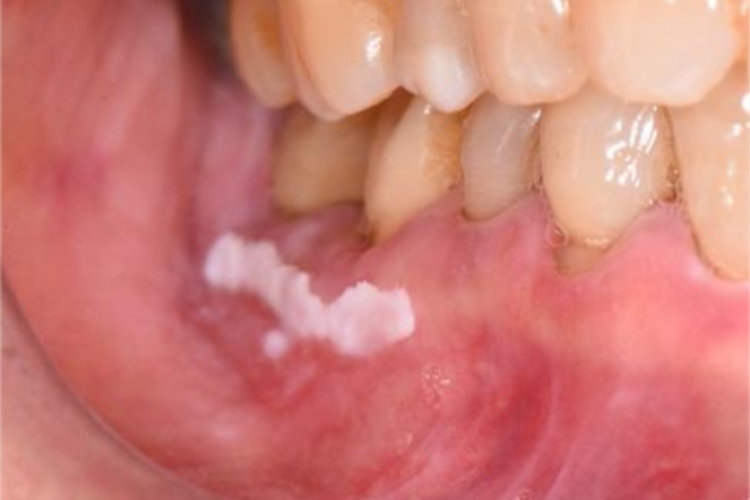

口腔白斑病可表现为牙龈处有稍高出黏膜表面的白色斑块,损害形态多样,触摸表面光滑,质地柔软,周围黏膜正常,患者无明显的自觉症状,偶尔有粗糙感或木涩感。